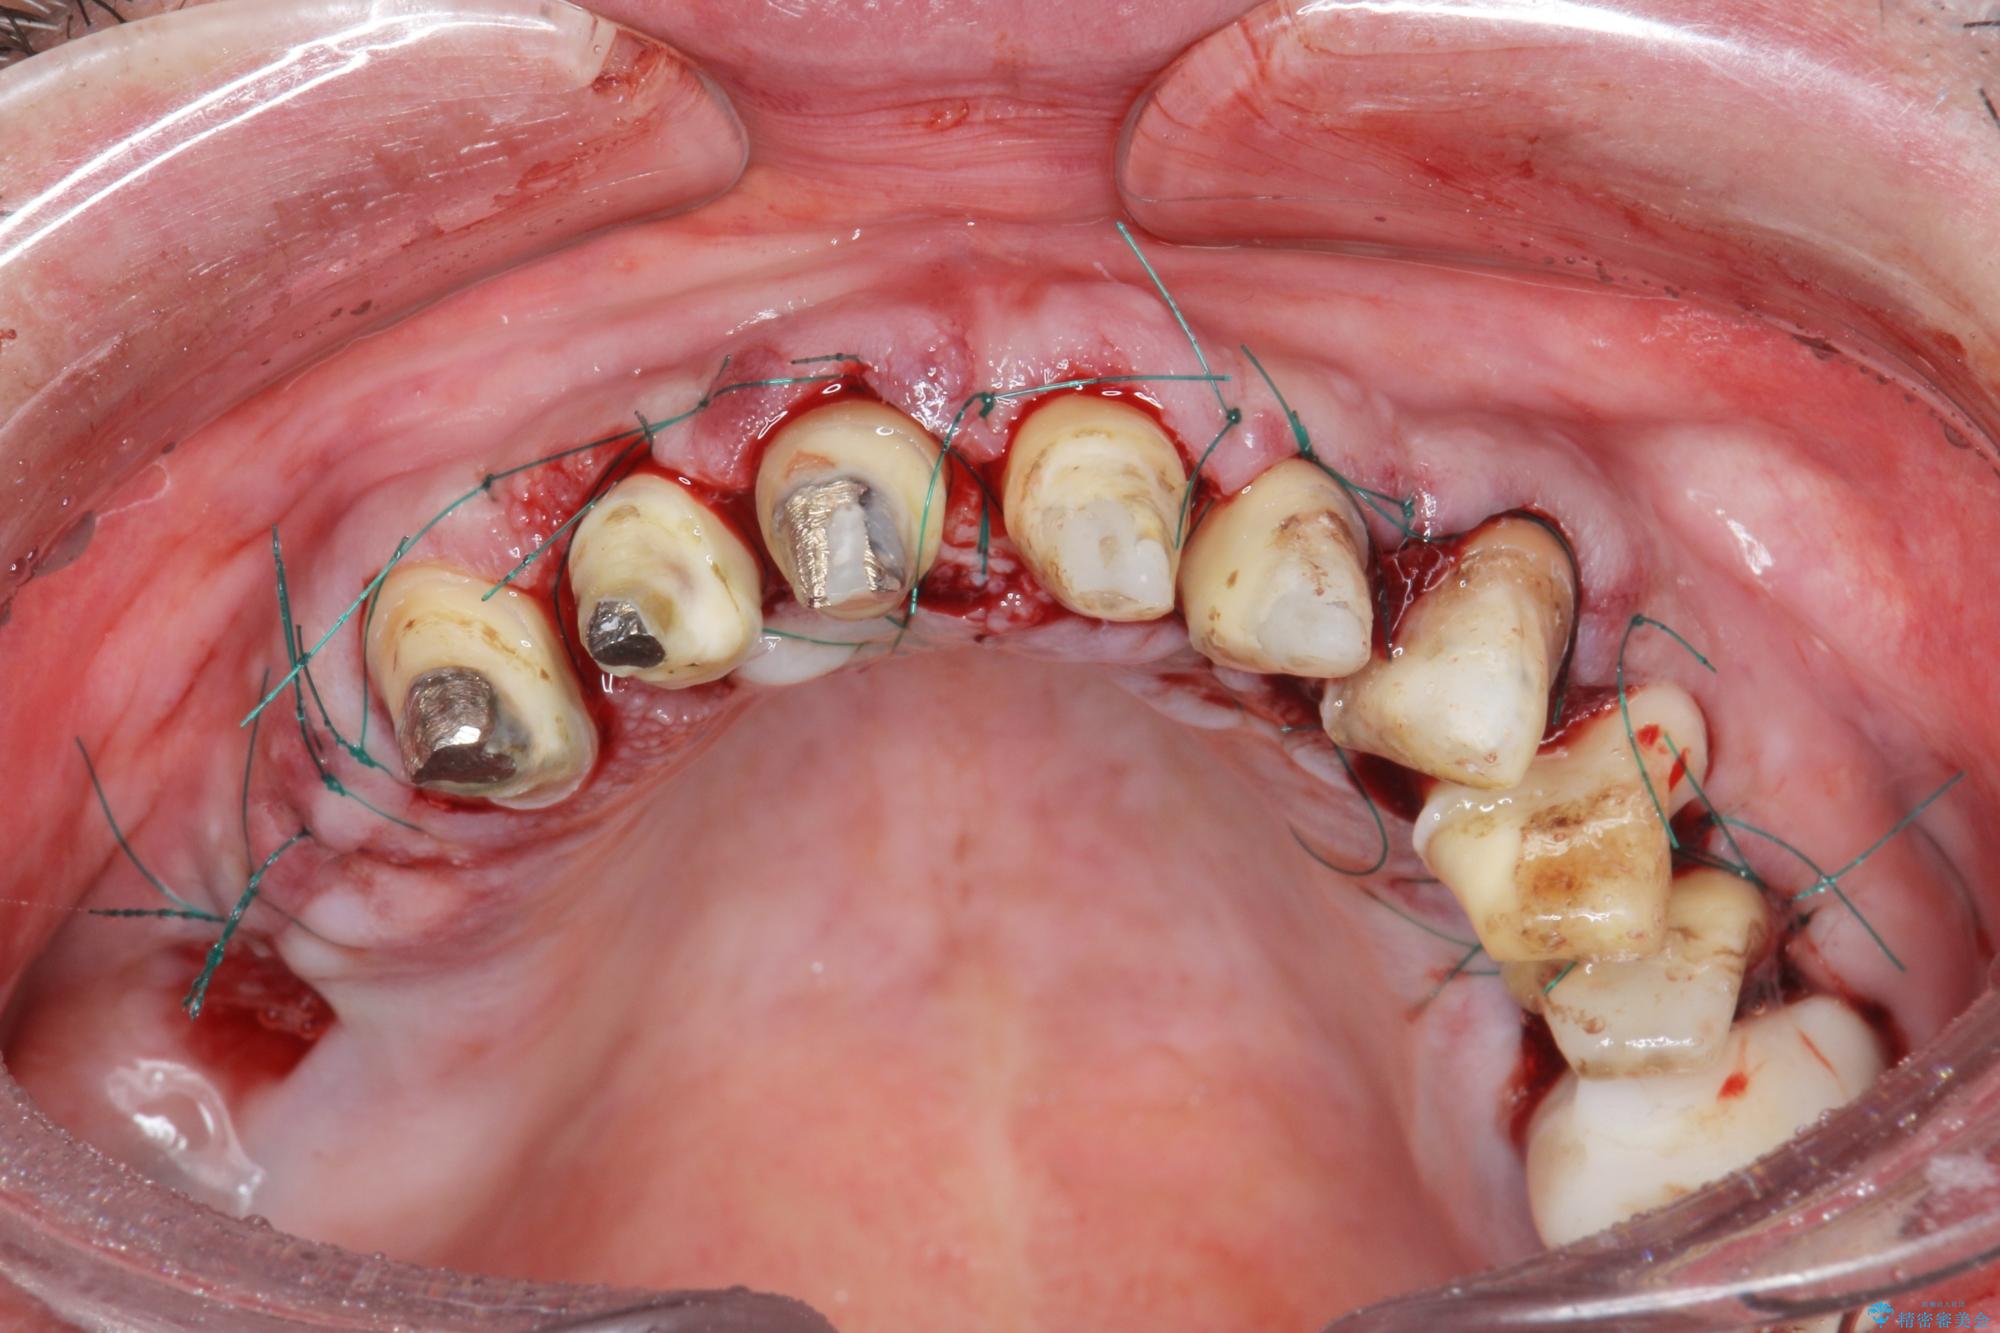

- 「セラミック治療を他院で受けたが、それ以来歯ぐきが腫れ違和感がある、改善してほしい。」と歯ぐきの状態改善を希望され来院されました。

歯周組織検査を行うと歯ぐきからは容易に出血し、X線検査より歯とセラミッククラウンの適合が悪い(ピッタリと合っていない)状態が示唆され、歯ぐきの炎症を惹起している状態でした。

セラミッククラウンを除去し仮歯を装着し、歯周外科手術を行い歯ぐきの状態を改善したのち、適合の良いセラミッククラウンを再作製をする治療計画としました。